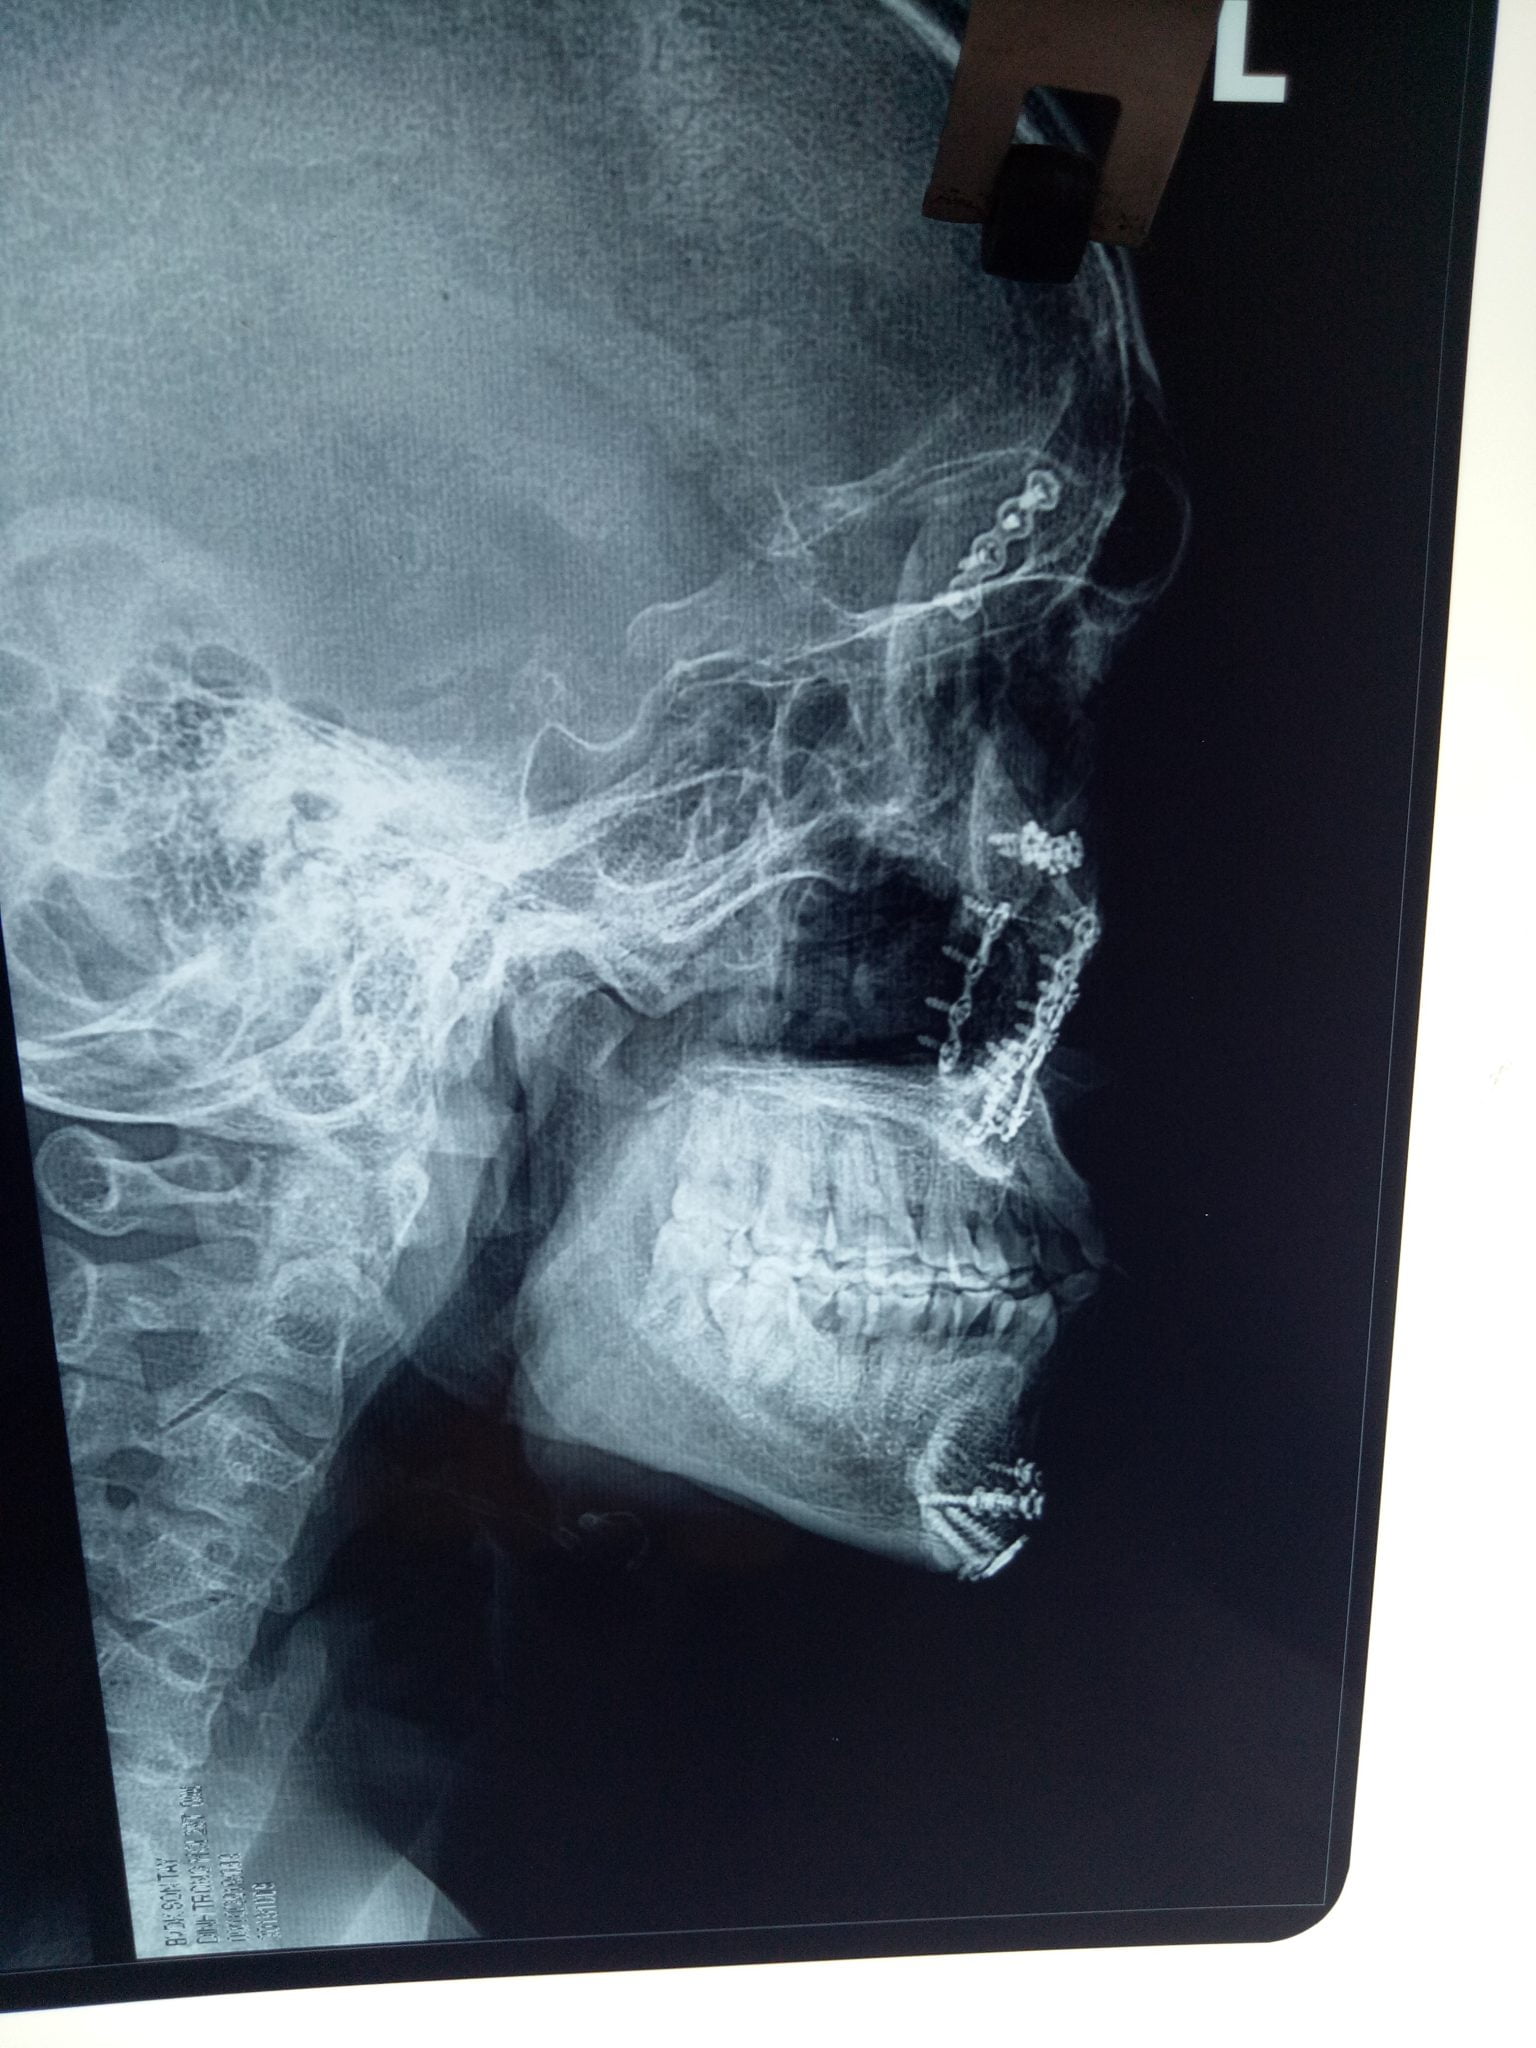

Phẫu thuật thành công số lượng lớn Nep+Vít vùng hàm mặt tại khoa Răng Hàm Mặt Bệnh Viện Đa Khoa Sơn Tây Hà Nội. Gồm có 9 nẹp titan+33 vít. Vừa qua kíp phẫu thuật khoa Răng Hàm Mặt đã phẫu thuật thành công cho bệnh nhâ:  Đinh Trọng  H  29t (Ba vì-Hà nôi )…

Gồm có 9 nẹp titan+33 vít.

Vừa qua kíp phẫu thuật khoa Răng Hàm Mặt đã phẫu thuật thành công cho bệnh nhâ:  Đinh Trọng  H  29t (Ba vì-Hà nôi )

Bệnh nhân H vào viện  ngày  09 .10.2019 . Phẫu thuật ngày  10.10.2019

Qua hỏi và thăm khám được biết bệnh nhân  H bị tai nạn giao thông  đã được phẫu thuật kết hợp xương>16 tháng tại bệnh viện Việt Đức, đến viện Sơn Tây  được khám và chụp CTScanner  có dựng hình 3D có hình ảnh can xương tốt đã được hội chẩn các bác sỹ trong khoa và hội chẩn với BS Cường Trưởng Khoa gây mê hồi sức đã tiến hành phẫu thuật lấy toàn bộ 9nẹp và 33 vít hàm mặt cho bệnh nhân đảm bảo thẫm mỹ tối đa cho người bệnh đường mổ được thực hiện hầu hết trong miệng.

Bác sỹ Hương Trưởng Khoa Răng hàm mặt cho biết đây là phẫu thuật lớn bệnh nhân  bị gãy phức hợp gò má cung tiếp phải + xương hàm trên 2 bên + xương hàm dưới, bệnh nhân còn trẻ nên các bác sỹ khoa Răng Hàm Mặt đã tiến hành đi đường trong miệng ,đường dưới ổ mắt  vị trí bờ mi dưới và cung mày trên giúp giảm tối đa seo sau mổ cho bệnh nhân.